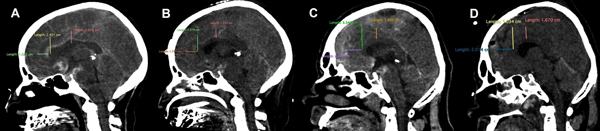

Finalmente, creemos que el uso de estas distancias puede ser una herramienta útil para la planificación quirúrgica en ciertas patologías. Por ejemplo para localizar lesiones en la fisura interhemisférica o en la superficie medial del hemisferio cerebral. Al poder ubicar el objetivo quirúrgico en la RM preoperatoria y medir en ese punto exacto la distancia entre el CC y el borde libre de la HC, esa medida puede reproducirse en el escenario quirúrgico luego de abrir la fisura interhemisférica. En otro procedimiento que se podrían utilizar estas mediciones es en la callosotomía posterior para casos de pacientes con epilepsia refractaria, donde a través de estas distancias podemos planificar la extensión anterior de nuestra callosotomía. Así mismo estas distancias podrían ser útiles para determinar la extensión de la resección ósea realizada en craniectomías descompresivas bifrontales para el tratamiento de la hipertensión endocraneana. En las craniectomías descompresivas bifrontales clásicas, los autores proponen una amplia resección ósea, ligar el 1/3 anterior del seno sagital superior y seccionar la HC para evitar el daño del CC, entre otras estructuras13. Dicho daño al CC es provocado por mecanismos que describimos anteriormente. Nuestro estudio demuestra con datos anatómicos, que la resección del puente óseo que cubre el seno sagital superior podría no ser realizada. También podría evitarse ligar el 1/3 anterior del seno sagital superior y seccionar la hoz, previniendo la morbi-mortalidad asociada a estos gestos quirúrgicos, ya que existe una distancia como mínimo de 1 cm entre el CC y el borde libre de la HC (figura 3). Esta última teoría deberá ser demostrada en trabajos prospectivos.

Figura 3: Presentamos dos casos de pacientes con hipertensión endocraneana refractaria al tratamiento médico en los cuales se realizó una craniectomía descompresiva bifrontal dejando el puente óseo que cubre el seno sagital superior, evitando de esta manera ligar el 1/3 anterior de este seno y seccionar la hoz. En ambos casos se midieron las distancias antes mencionadas, tanto en las imágenes pre- quirúrgicas como en las post-quirúrgicas, no encontrándose grandes variaciones.

A: Caso 1 imagen pre-quirúrgica y mediciones de las distancias antes mencionadas B: Caso 1 imagen post-quirúrgica y mediciones de las distancias antes mencionadas C: Caso 2 imagen pre-quiúrgicas y mediciones de las distancias antes mencionadas D: Caso 2 imagen post-quiúrgica y mediciones de las distancias antes mencionadas